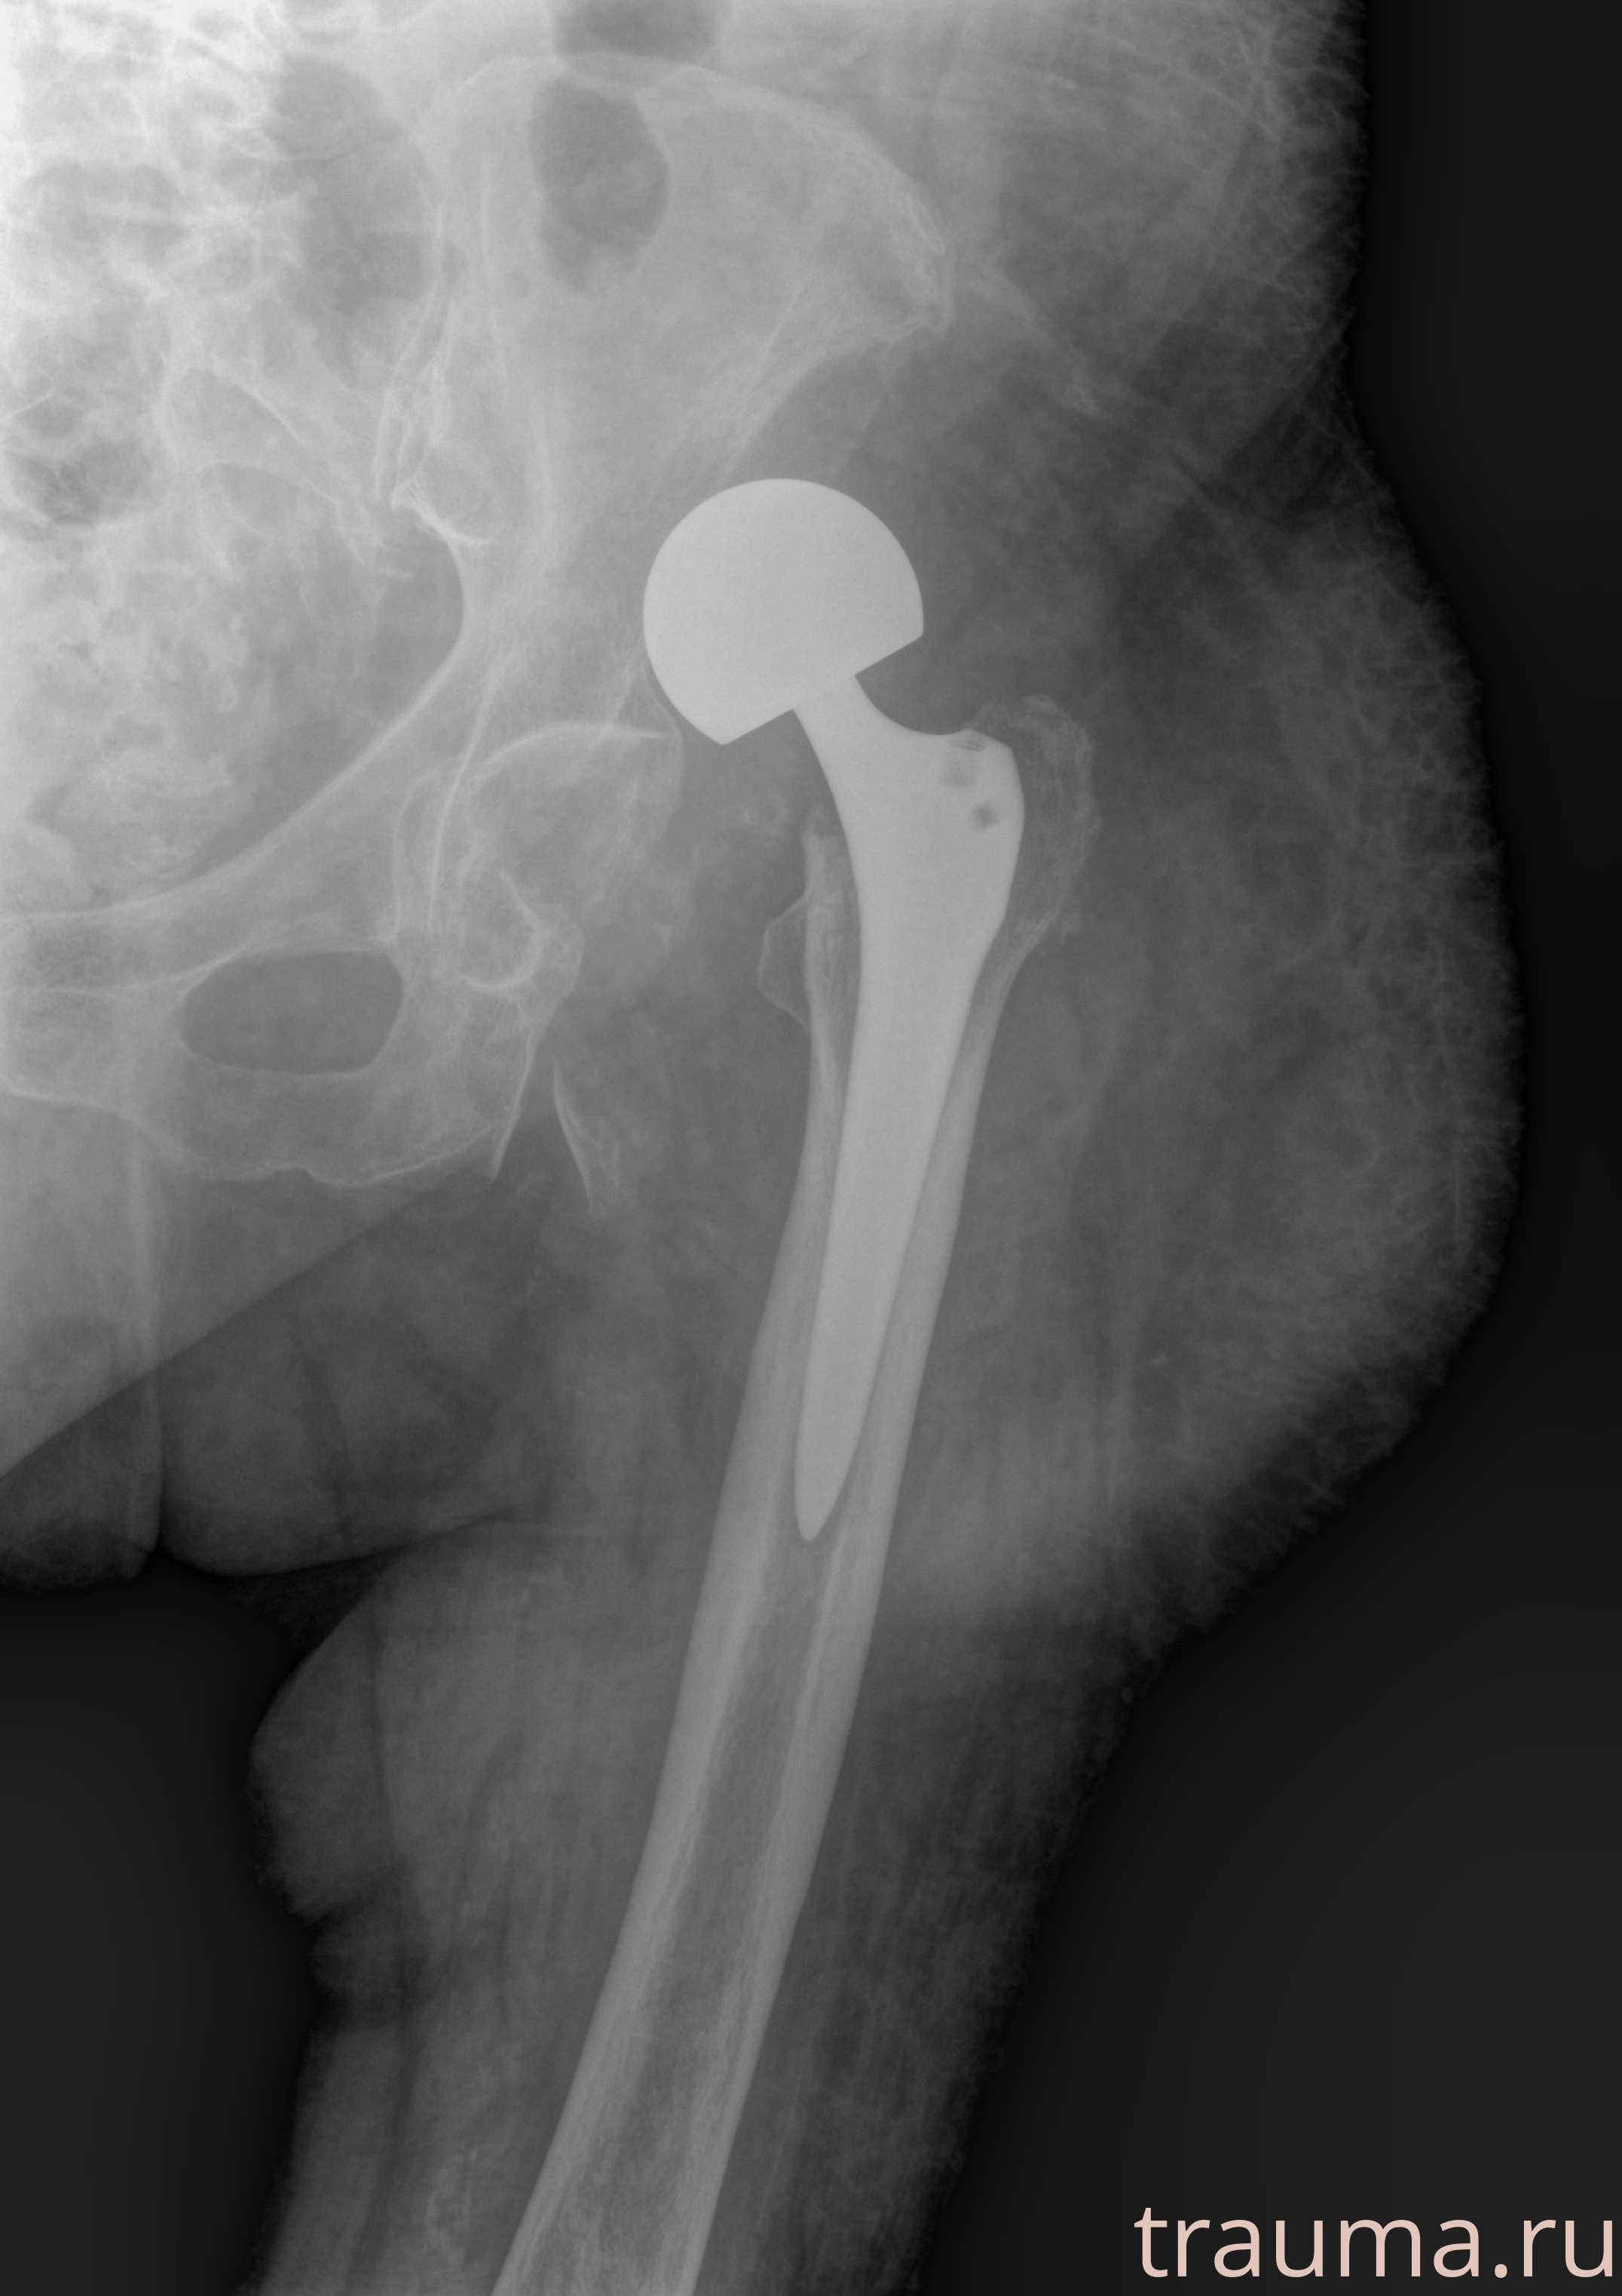

Первая помощь при переломе шейки бедра

Рентгенограммы

Рентген на дому: по вашему адресу приезжает врач-рентгенолог, травматолог-ортопед с мобильным рентгеновским аппаратом, проводит диагностику травмы или заболевания, делает необходимые рентгенограммы, дает рекомендации по дальнейшему лечению. Получить качественные снимки в домашних условиях возможно благодаря уникальной методике, разработанной МосРентген Центром для института  Склифосовского

при переломе шейки бедра и пневмонии от компании МосРентген Центр - партнера Института имени Склифосовского